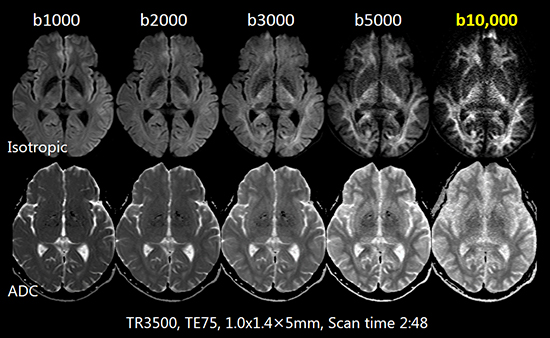

High Power Gradient

高い傾斜磁場強度(Gmax)により,拡散強調画像のTE短縮を実現し,高b値の撮像も可能にします。高分解能画像においてもパラメータ設定の自由度が向上し,高品質な画像を提供します。

高精度Gradient

冷却能力や剛性を高めたGradientにより,ハイパワーでありながら渦電流の発生や発熱,振動を大幅に低減しました。Direct Sagittal撮像でも歪みの少ない拡散強調画像が得られます。